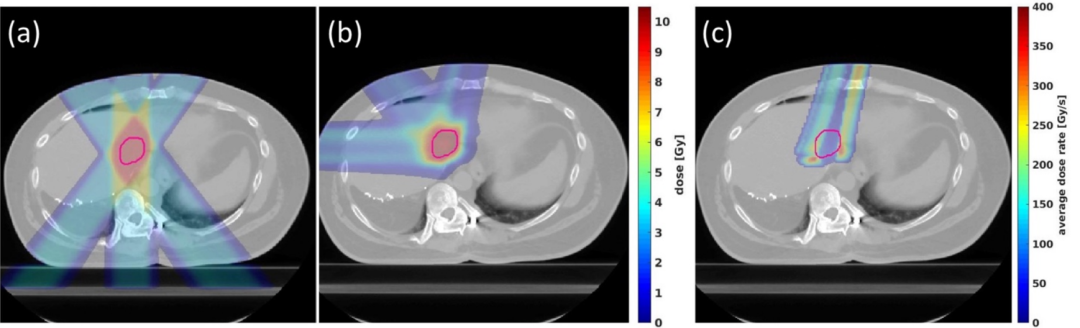

圖4.透射式和布拉格峰式肝癌的FLASH質子計劃二維劑量分布比較。(a)典型的FLASH質子PBS透射式計劃;(b)典型的單能質子PBS布拉格峰式FLASH肝癌計劃,計劃中的劑量處方為每分次10 Gy;(c)一個單能質子布拉格峰式計劃射野的平均劑量率分布,結果顯示大于40 Gy/s的平均劑量率分布能夠在大部分正常組織中實現